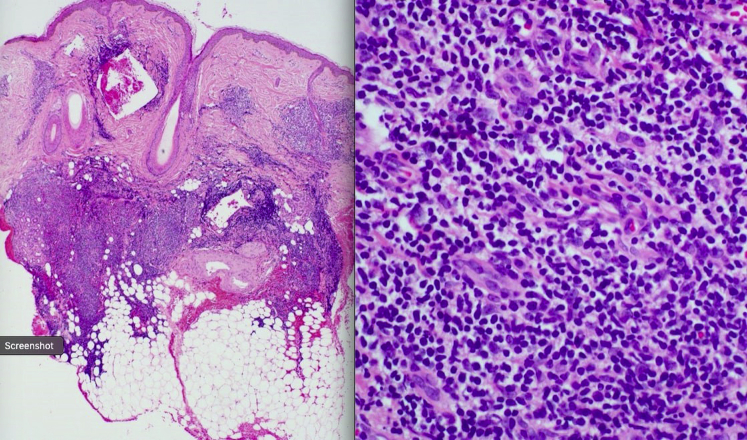

Fig 2.

Hematoxylin–eosin staining of a punch biopsy specimen at ×5 magnification showing dense nodular lymphocytic infiltrates in the dermis and superficial subcutaneous fat.